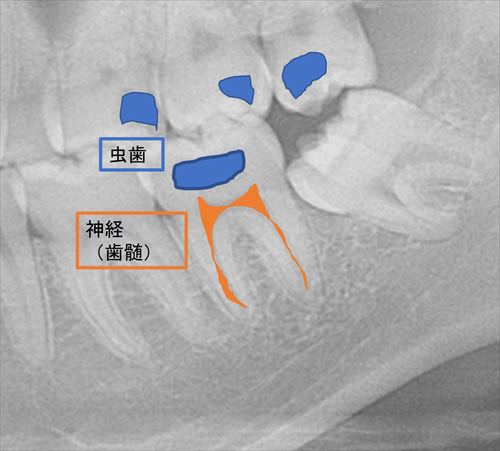

レントゲンで診ると大きな虫歯がみられます。

レントゲンの解説です。青く塗った部分がすべて虫歯です。

今回は下の歯の治療を行います。虫歯が大きくなり、神経に近接しています。